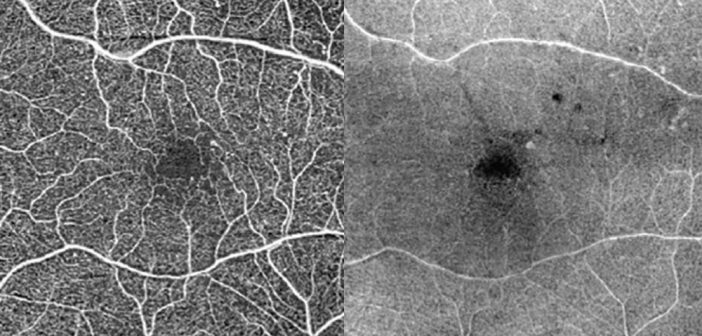

L’OCT-angiographie (OCT-A) fournit une analyse de la structure et de la localisation des anomalies microvasculaires associées à la rétinopathie diabétique (RD) : microanévrismes, anomalies microvasculaires intrarétiniennes (AMIR). Il identifie et caractérise, par ailleurs, les complications de la RD : œdème maculaire (OM) et néovaisseaux [1, 2]. Sur le plan physiopathologique, l’OCT-A a également permis de mieux comprendre certains mécanismes[...]